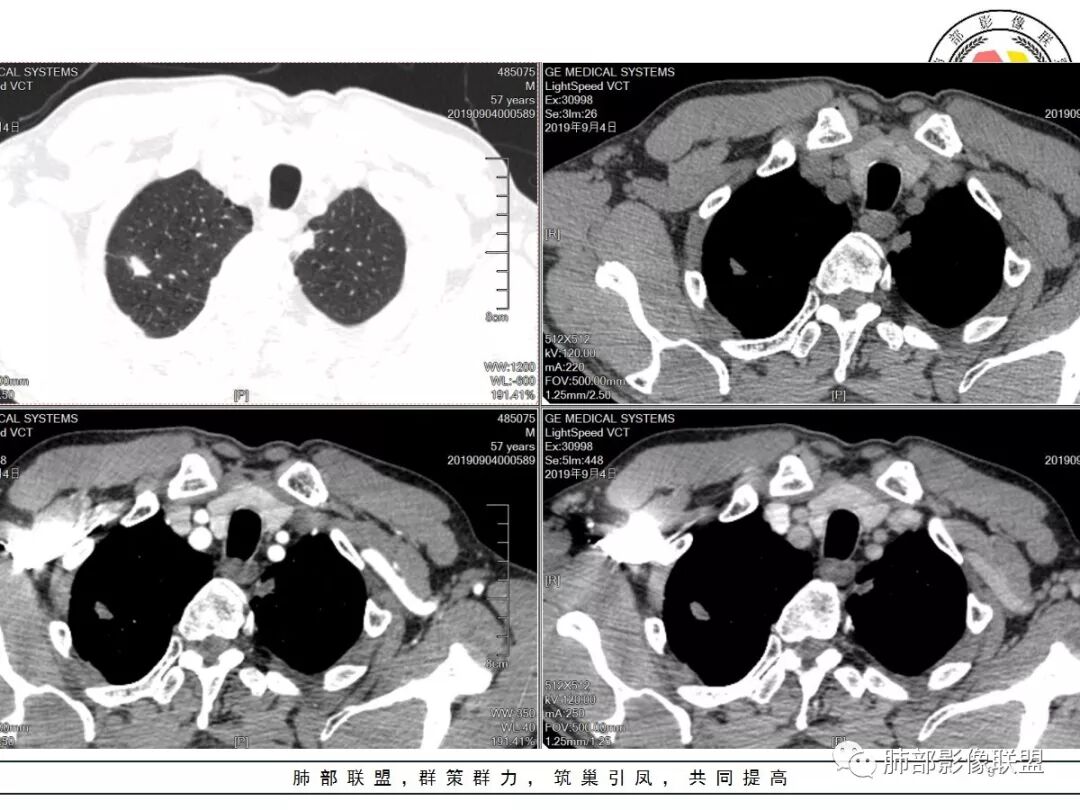

老年男性,体检发现,右肺上叶尖段类圆形结节

小叶中心型肺气肿背景,一般提示吸烟

周围有类似小结节

小斑片

根据周围常规:我们要考虑结核的可能

我们再看右肺上叶这个较大病灶主体

类圆形,浅分叶

胸膜凹陷

血管纠集

局部凸起

强化幅度超过20HU

边缘平直

南边:

有炎性的特点,但是确实存在恶性征象

我觉得恶性最起码不能排除,要考虑,最起码要建议临床干预

一般我的观点:多发炎性征象,如果合并有恶性征象,就不能排除恶性

1.应该是双肺上叶多发结节,散在大小不等,密度不均,左上纵隔旁病灶环形强化,似乎都符合结核灶。

2.焦点在乎右肺上叶那个有点另类、有点儿一本正经的结节,密度均匀,未见支气管进入,部分圆隆浅分叶,长毛刺或棘状突起,胸膜有点牵拉,像个特立独行的新生物吗?

3.最不支持腺癌的一条是强化程度太轻。此外分叶不典型,还有那条牵张于肺表面的长长的细线影,不大像是在牵拽。

4.小结节新生物不大容易观察到液化坏死,如观察到液化坏死更容易想到的也是结核。

因此,完全排除肺鳞癌还有相当难度的。